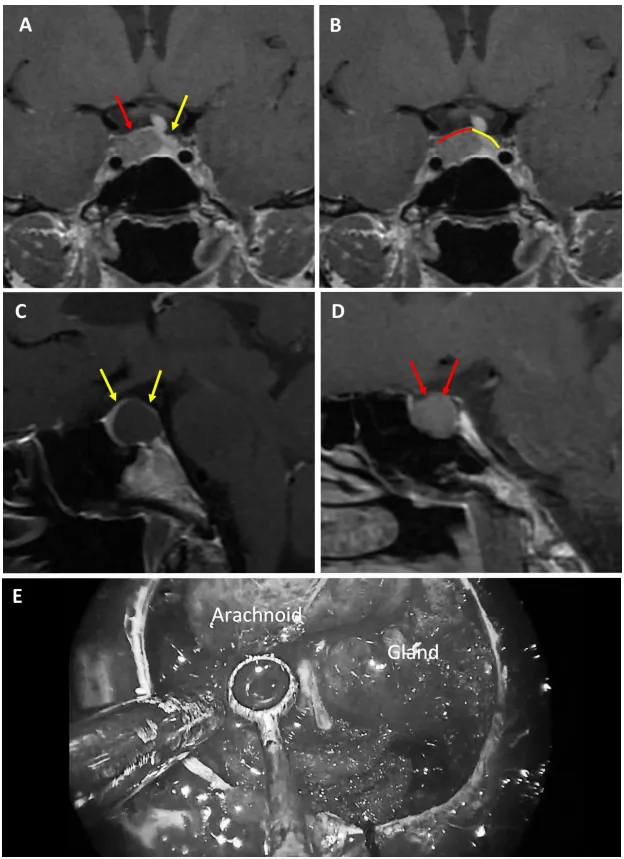

3薄弱型鞍隔屏障案例

圖6

圖6:59歲女性泌乳素腺瘤患者。a、b術(shù)前MRI:紅色箭頭指示厚度小于1毫米的強化屏障區(qū)。c、d術(shù)前MRI:紅色標記線標示薄弱屏障位置。e、f術(shù)中圖像:可見由蛛網(wǎng)膜構(gòu)成的屏障結(jié)構(gòu)。

圖7

圖7:69歲女性生長激素腺瘤患者。a、b術(shù)前MRI:黃色箭頭指示厚度小于1毫米的強化屏障區(qū)。c、d術(shù)前MRI:紅色標記線標示薄弱屏障位置。e、f術(shù)中圖像:可見由蛛網(wǎng)膜構(gòu)成的屏障結(jié)構(gòu)。